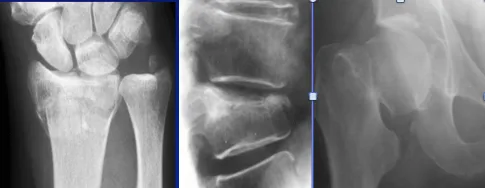

Typical osteoporotic fractures in the wrist, spine & hip